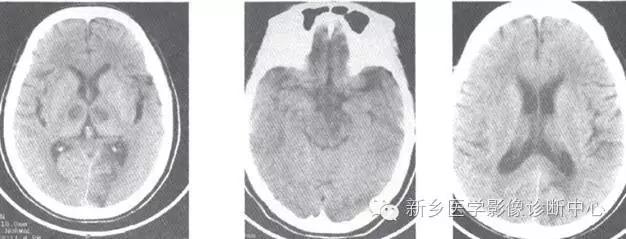

影像表现

影像表现:

脑部CT、MRI检查,显示累及基底动脉尖部5条血管供血区的2个以上梗死灶。常见部位依次为:丘脑、中脑、小脑、枕叶、颞叶等。

最大特征为双侧丘脑梗死,病灶位于丘脑中心部位,成蝶形、对称性分布。